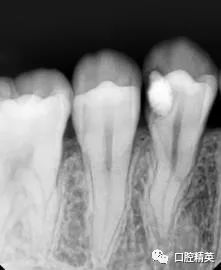

左下后牙急性牙髓炎1例

221x270 - 7KB - JPEG